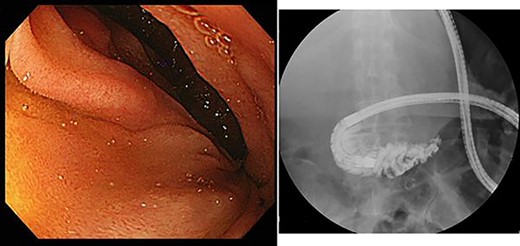

A 75-year-old bedridden woman presented to our hospital with chief complaints of epigastric pain, anorexia and a palpable mass in the epigastric region. She had a history of surgery for meningioma, but no history of abdominal surgery. Ultrasonography revealed a well-defined large cystic lesion with a long diameter of approximately 150 mm in the left liver lobe. Contrast-enhanced computed tomography showed a giant hepatic cyst with an irregular mass in liver segment 4, 20 × 16 cm in size (Fig. 1).

Upper gastrointestinal endoscopy showed severe duodenal stenosis due to compression from outside of the wall, which was the cause of gastric pain and anorexia (Fig. 3).

Upper gastrointestinal endoscopy showed severe stenosis of the duodenum.